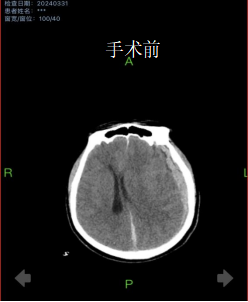

4月初,81岁的齐爷爷不慎从床上跌落,家人发现时已意识不清,急送医院就诊。完善CT检查后提示重度颅脑损伤,左侧大量硬膜下血肿。手术指征明确,由于患者病情危重,随时有呼吸心跳骤停可能,神经外科二病区主任姚胜及主治医生朱奕儒评估病情后,立即为患者行开颅手术。术后,护理团队为老人提供了优质、温馨的护理服务,齐爷爷在昏迷几天后逐渐清醒,没有留下肢体、语言等方面后遗症,痊愈出院。